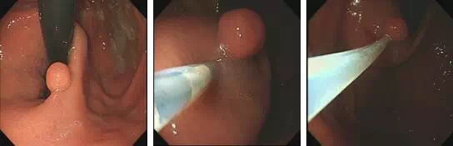

热活检钳电凝钳除术

热活检钳有什么作用【健康科普】发现胃肠息肉,到底要不要切?_https://www.jmylbn.com_新闻资讯_第7张

1. 发现息肉 2.热活检钳夹住息肉 3.钳除息肉